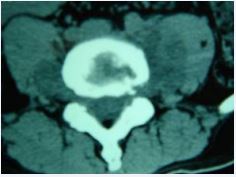

In 13 patients (18.57%), the bone at the edge of the vertebral body was stiffened like a bird’s beak, which was connected with the edge of adjacent vertebral body hyperplasia to form a bone bridge, and 11 patients (15.71%) had poor lumbar stability. CT showed 53 cases (75.71%) patients with vertebral edge disease have size about 2~6 mm multiple focal bone destruction, bone destruction around focal sclerosis of bone hyperplasia, bone of new born stove and new bone broken, the whole edge vertebral bodies like lace structure formation “lace vertebral (Figure 3)”; In 17 cases (24.28%), intervertebral disc lesions showed isodense shadows, articular cartilage surface sclerosis and hyperplasia, proliferated bony protruding toward the edge of the vertebral body to form “lip”-shaped osteophytes, anterior longitudinal ligament and paravertebral sides were calcified, and there were osteophytes connect (Figure 4); In this group, 18 patients (25.71%) had widened paravertebral muscles with abscess formation and clear surrounding space, but no abscess drainage imaging (Figure 5).

MRI showed that 70 patients with diseased vertebral bodies and intervertebral discs showed heterogeneous signals, in 18 cases, paraspinal features were thin and irregularly enhanced abscess walls and abnormal signals in poorly defined soft tissues, T1WI showed low signal, and T2WI showed high signal; Eleven patients had poor lumbar spine stability and spondylolisthesis; 42 patients showed uneven hypersignal in the vertebral body, intervertebral disc, and spinal canal on T1WI, T2WI, and fat pressure images, and the corresponding plane dura or nerve root compression (Figure 6).